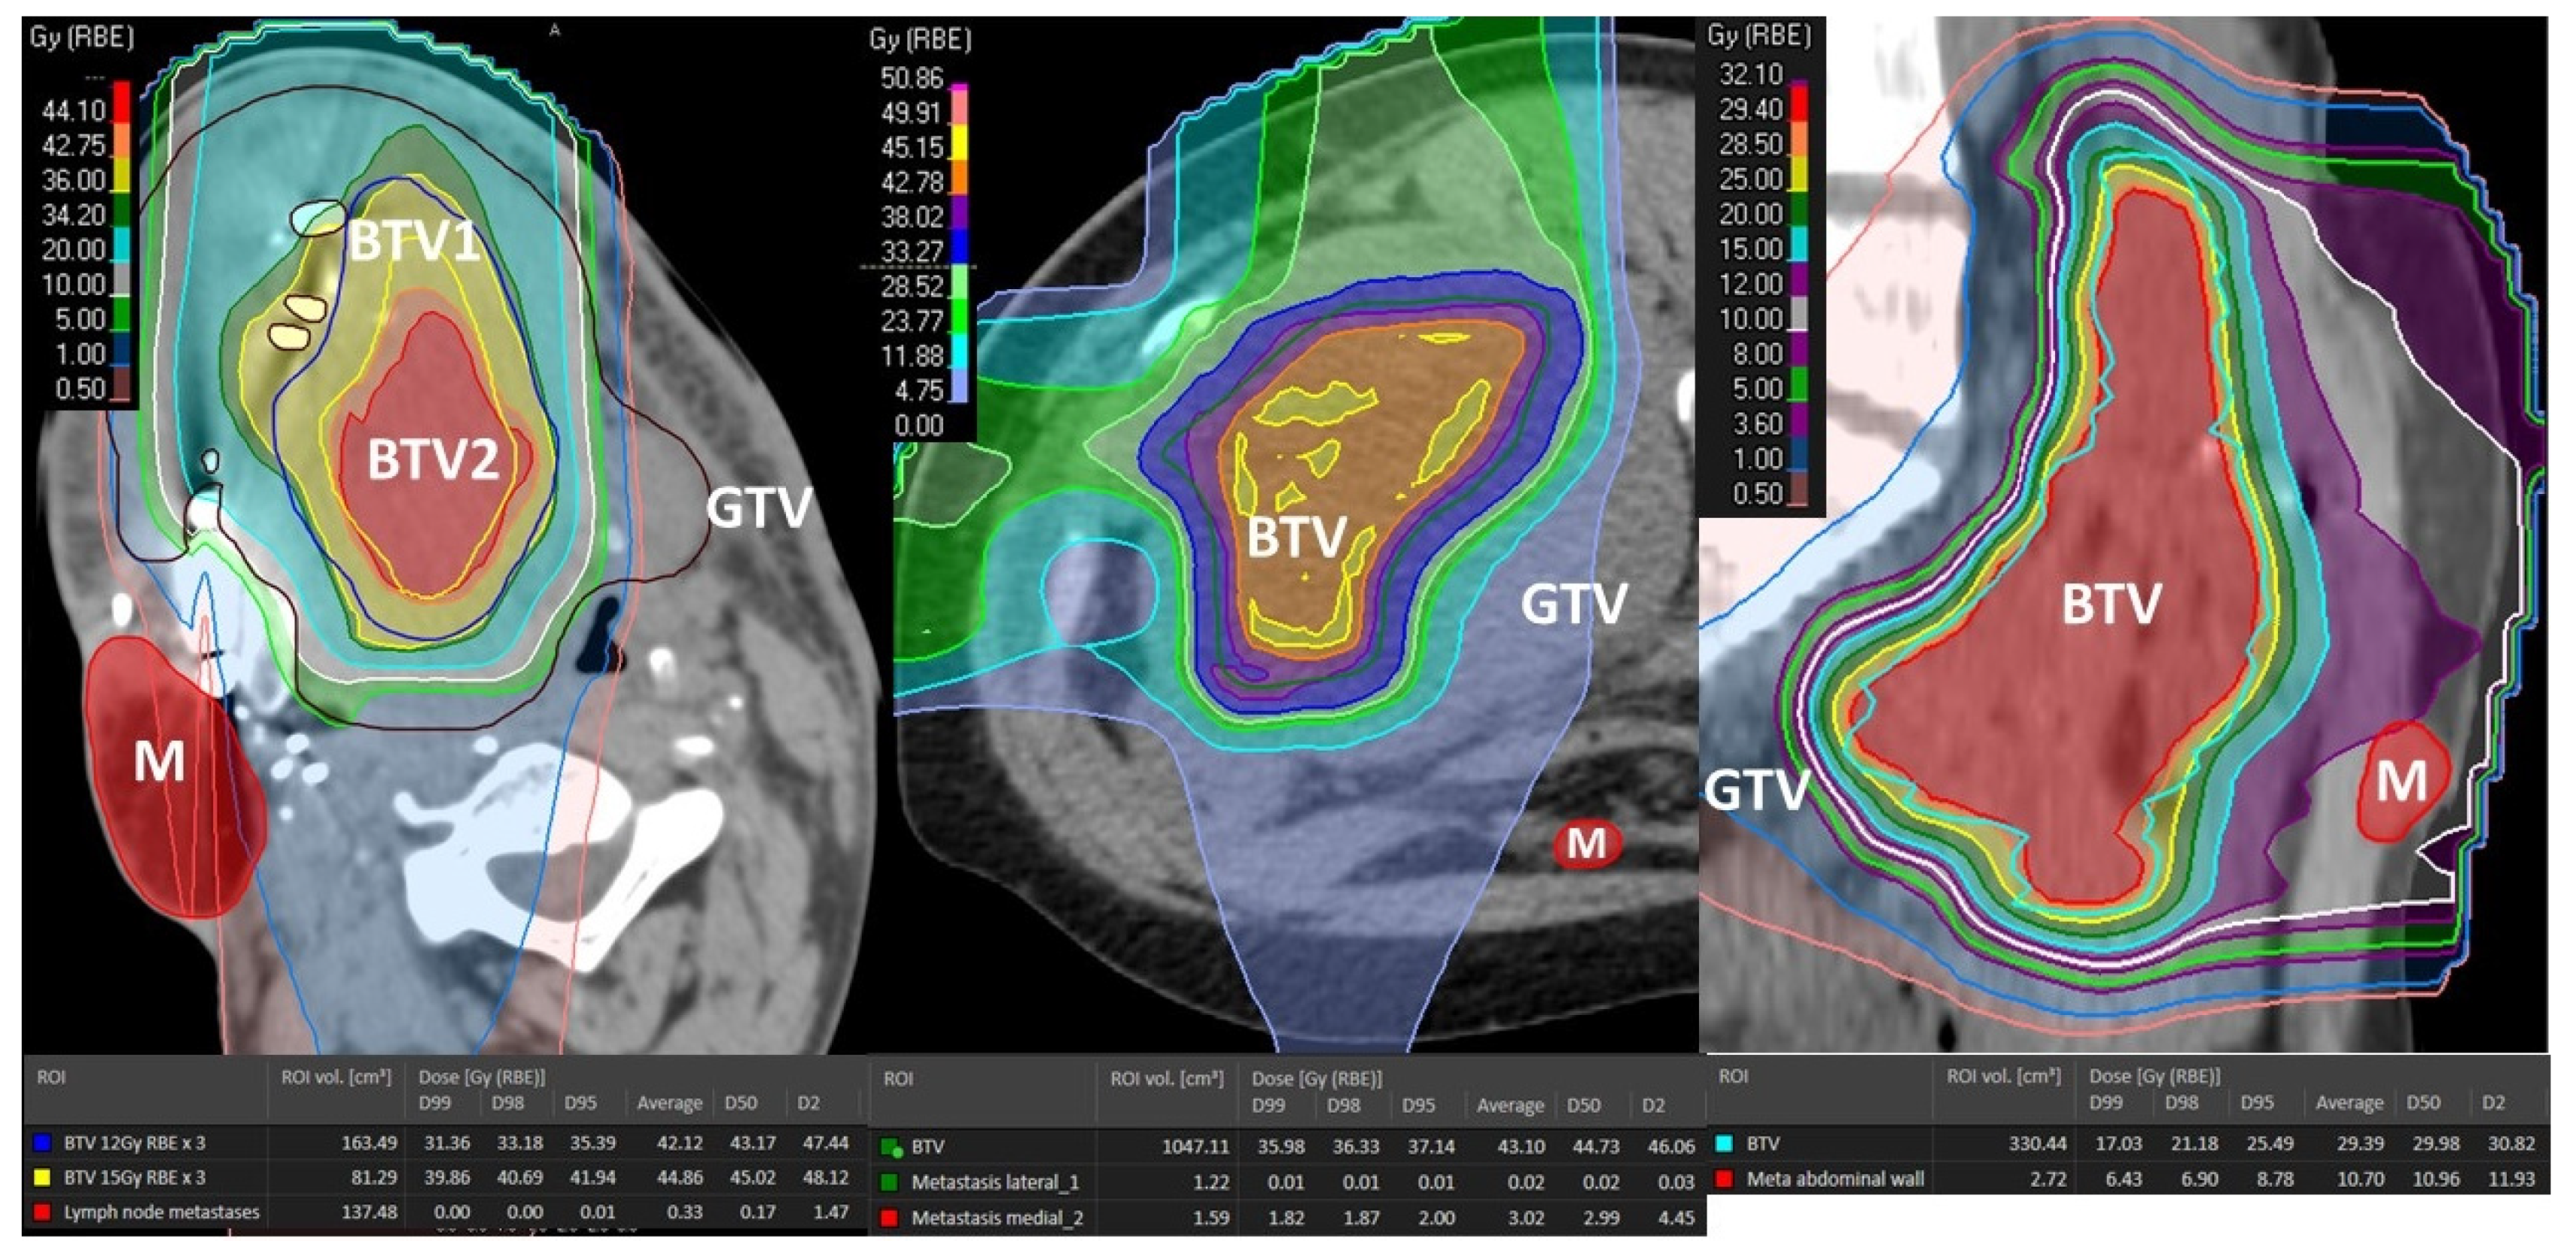

Figure 2. Delineation of the Bystander Tumor Volume (BTV) and Peritumoral Immune-Microenvironment (PIM): (A) the figure shows the principles of the target delineation for Particle-PATHY treatment. After the Gross Tumor Volume (GTV, red dotted line) has been defined, the BTV-partial tumor volume (green line) as the target for PATHY irradiation has been created by subtracting 1 cm from GTV surface in all directions reducing the GTV volume to the 30% (+/−3%). PIM (yellow line) was created by adding a uniform 1 cm margin to the GTV and then subtracting the same GTV to create “a ring” that surrounds the GTV; (B) In those patients affected by particularly large tumors two tumor sub-volumes BTV1 and BTV2, respectively, were delineated whereby the BTV2 was created by subtracting 1 cm from BTV1 (or 2 cm from GTV surface) in all directions.

Volumes definition: The targeted internal partial tumor volume is termed “Bystander Tumor Volume” (BTV). Its delineation was adopted from previously published studies on photon-based SBRT-PATHY [7,8]. Since in those series the BTV corresponded on average to the centrally located approximately 30% of Gross Tumor Volume (GTV), in this study it was created by subtracting 1cm from the GTV surface in all directions until reaching 30% (+/−3%) of the GTV volume (Figure 2). No additional margins, neither for the Clinical Target Volume (CTV) nor for Planning Target Volume (PTV), were applied to the BTV since the objective of this treatment was to irradiate a tumor sub-volume in order to effectively spare the peritumoral immune system cells. No hypoxia-specific tumor imaging, which is planned for future patients, was utilized in this present group. However, the majority, if not all, of the hypoxic tumor segments were likely covered by the BTV volume since in all cases the central, necrotic and perinecrotic tissues were included in the BTV.

Once the BTV was defined, the PIM was created (Figure 2A,B). The PIM, containing the loco-regional infiltrating immune system cells as the mediators of the non-targeted radiation effects, was considered an OAR (Organ At Risk). The PIM was created by adding a uniform 1 cm margin to the GTV and then subtracting the same GTV to create “a ring” that surrounds the GTV. The goal of treatment planning was to keep the dose within the PIM as low as reasonably achievable but considering the following dose constraints as the planning objective: Dmean < 6 Gy, D20 < 0.5 Gy, D30 < 1 Gy and D50 < 3 Gy in three fractions. Additionally, all nearby regional vascular supply and lymph node stations were included if they were within the 2 cm-distant areas from the GTV.

To deliver sufficiently high and possibly heterogeneously distributed radiation dose at the level of the targeted BTV. The intended dose was in the order of 10–15 Gy per fraction. In order to address heterogeneity in radiation dose delivery, dose-gradients were created within the BTV, by creating an additional BTV (BTV2) within the former BTV (BTV1) by subtracting 5 mm from the BTV1 surface in all directions whenever tumor volume would permit it (Figure 2B and Figure 3B).

Achieving the BTV prescription goal was subordinated to the possibility of creating a sufficiently sharp dose fall off between the BTV surface and the GTV surface surrounded by the PIM and was proportional to the thickness of peripheral tumor tissue in between the BTV and GTV surfaces. Treatment plans were calculated to deliver 30–36 Gy in three consecutive fractions (10–12 Gy per fraction) to the BTV1, and 36–45 Gy (12–15 Gy per fraction) to the BTV2 so that at least 95% of the BTVs received as minimum 95% of the prescription dose. The choice of prescribing the fractional doses was driven by PIM-sparing: 12 Gy to the BTV1 with 15 Gy to the BTV2 were preferred if allowing planned PIM-sparing which was easier to achieve in particularly large tumors. Otherwise, the fractional dose was reduced to 10 Gy to the BTV1 with 12 Gy to the BTV2 to lower the dose received by PIM. In those patients in whom neither of the two goals was possible, only one BTV (BTV1) was created and treated either with 12 Gy × 3 or 10 Gy × 3 (Figure 2A and Figure 3A). Reported doses in Gy are RBE-weighted doses calculated from the physical dose using the LEM model for carbon ions [22] while for protons a fixed RBE of 1.1 was assumed.

Treatment characteristics are summarized in Table 3. Irradiated bulky-tumor sites were skull base (18%), head and neck (18%), lung (9%), abdomen (27%) and pelvis (27%). All three treated abdominal lesions were intraperitoneal. Mean tumor diameter and volume were 15.6 cm (range 6–27.5) and 1460 cc (range 76–5645.9), respectively. The mean volume of targeted BTV was 431.7 cc (range 36.1–1494) representing on average 29.6% of the mean GTV volume; i.e., approximately 1/3 of the GTV was targeted. Six patients (54%) were treated with 10 or 12 Gy delivered three times on consecutive days to the single BTV volume (BTV1). However, in the remaining five patients (46%) affected by particularly large tumors the dose corresponding to 10 and 12 Gy or 12 and 15 Gy was delivered three times to two tumor sub-volumes (BTV1 and BTV2), respectively (Figure 2 and Figure 3). Seven patients (64%) were treated with mixed proton and carbon ion therapy while four of them either with full proton (18%) or carbon ion (18%) therapy. The “immune-dose” in terms of the PIM-sparing was as low as it was initially intended: the total average mean dose was 5.8 Gy, D50 ≤ 2.8 Gy, D30 ≤ 0.7 Gy and D20 ≤ 0.2 Gy in three fractions.